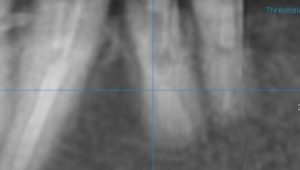

【フィステルから造影剤を挿入 病巣は根尖ではなく遠心側にある】

【CT画像でも遠心側に病巣】

【根尖には透過像がない】

【明らかに遠心側に透過像がある】